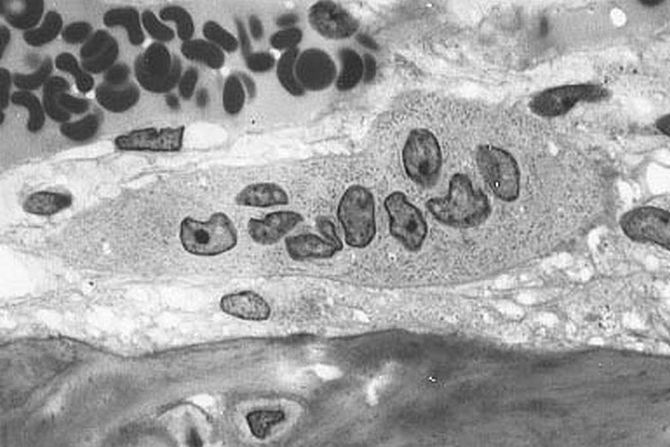

Istraživači su stimulisali TRIM putem beta-glukana, jedinjenja u izvesnim gljivicama, i merili su stvaranje osteoklasta, koji resorbuju kost tokom rasta i zarastanja, u modelima zapaljenjskog perodontitisa i artritisa.

Otkriveno je da taj tretman navodi prekurzore da se diferenciraju u osteoklaste brže ako je prisutan zapaljenjski izazov poput artritisa. Dakle, iako TRIM može imati korisne efekte – štiteći od infekcija i kancera – nalazi ukazuju da pamćenje ranije infekcije takođe može doprineti inflamatornim bolestima i komorbiditetu poremećaja inflamatornog gubitka koštane mase.